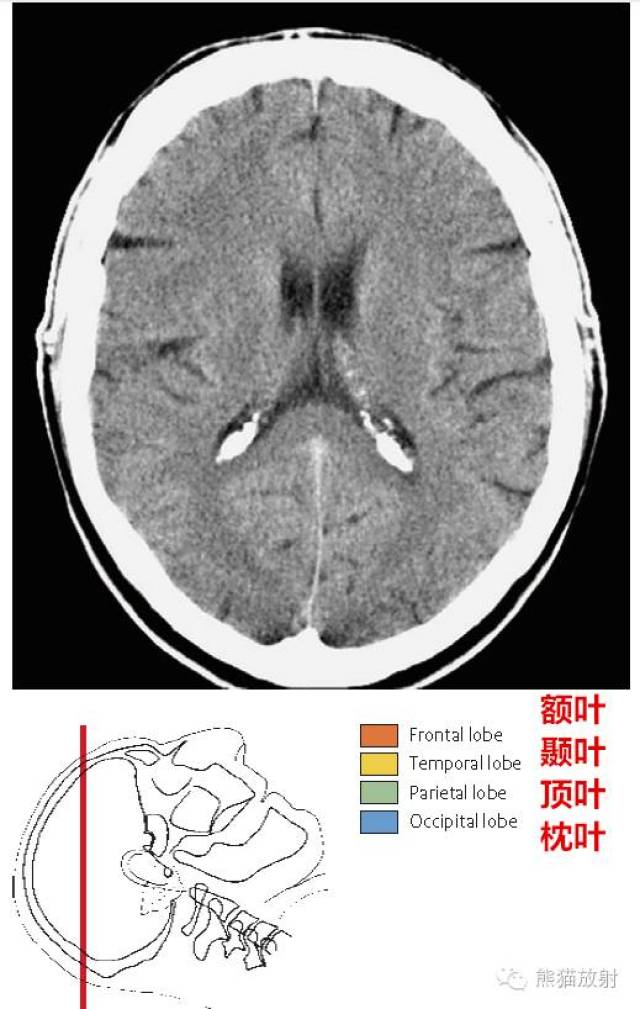

解剖入门颅脑ct断层中英文对照

图片尺寸552x814